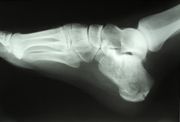

Skiagrafie

Skiagrafie je technika zobrazení lidských tkání, využívající rozdílnou hodnotu pohlcení procházejícícho svazku rentgenového záření v různých tkáních. Ze získaného obrazu pak lze ohodnotit jednak vnitřní stavbu vyšetřovaného orgánu, jednak jeho případná poranění. Pokud je obraz orgánu pouze pozorován bez zachycení na film nebo jiné záznamové médium, mluvíme o skiaskopii. Nejčastěji je skiagrafie využívána pro vyšetření kostí a zubů. Dříve časté (i screeningové) snímkování plic je nahrazováno jinými metodami. Pro skiagrafické snímkování se používají speciální rtg. filmy s výrazně silnější emulzní vrstvou a vyšším podíílem halogenidů stříbra. Tím je zajištěn požadovaný vyšší kontrast, zlepšující citlivost metody. Filmy jsou ukládány do skiagrafických světlotěsných kazet. Kazeta je na povrchu opatřena nosičem symboliky – vhodně přizpůsobenými místy pro vkládání stranových a popisných kovových značek, identifikujících jednak snímek, jednak jeho orientaci. Film je vyvoláván vysoce koncentrovanou vývojkou, opět s cílem získání nejvyššího možného kontrastu. Vzhledem k tomu, že skiagrafické přístroje jsou (kromě úzce specializovaných zařízení) navrhovány jako univerzální, pracují s vysokoenergetickými rentgenkami a pro snížení radiační zátěže obsluhy i pacientů je nutné používat filtrování a clonění rtg svazku. Primární filtr bývá umístěn blízko rentgenky a slouží pro pohlcování nízkoenergetických fotonů, sekundární (Buckyho) filtr se umisťuje mezi pacienta a filmovou kazetu, kde funguje jako past na rozptýlené fotony – propouští pouze záření ve směru rentgenka-film.